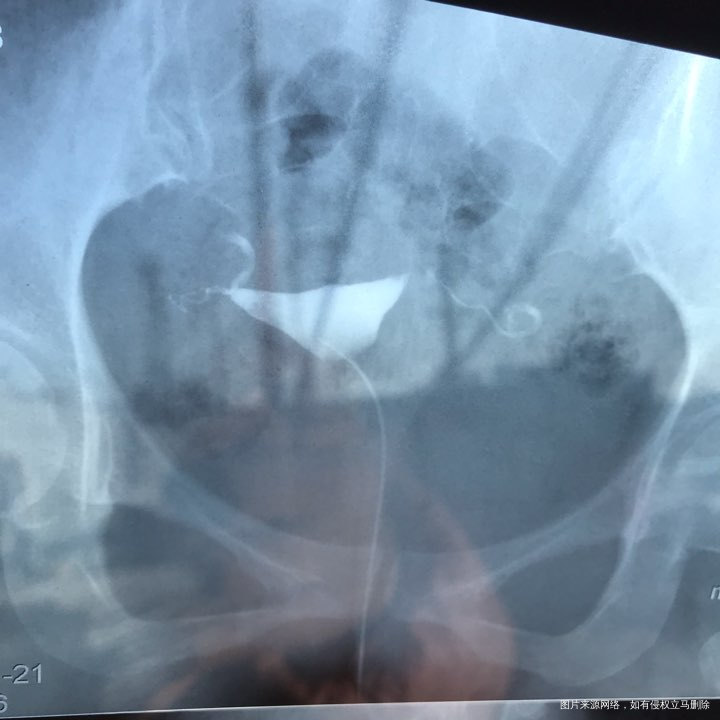

备孕时常1年,前期的检查都做了正常,帮忙看下我的输卵管造影片子吧??

您好,看着像是伞端堵塞了。

您好,考虑输卵管堵塞。建议遵医嘱。

您好,输卵管堵塞,建议切除输卵管做试管,保守保守治疗没有多大意义,觉着我的回复对您有帮助记着帮忙点击采纳,谢谢!